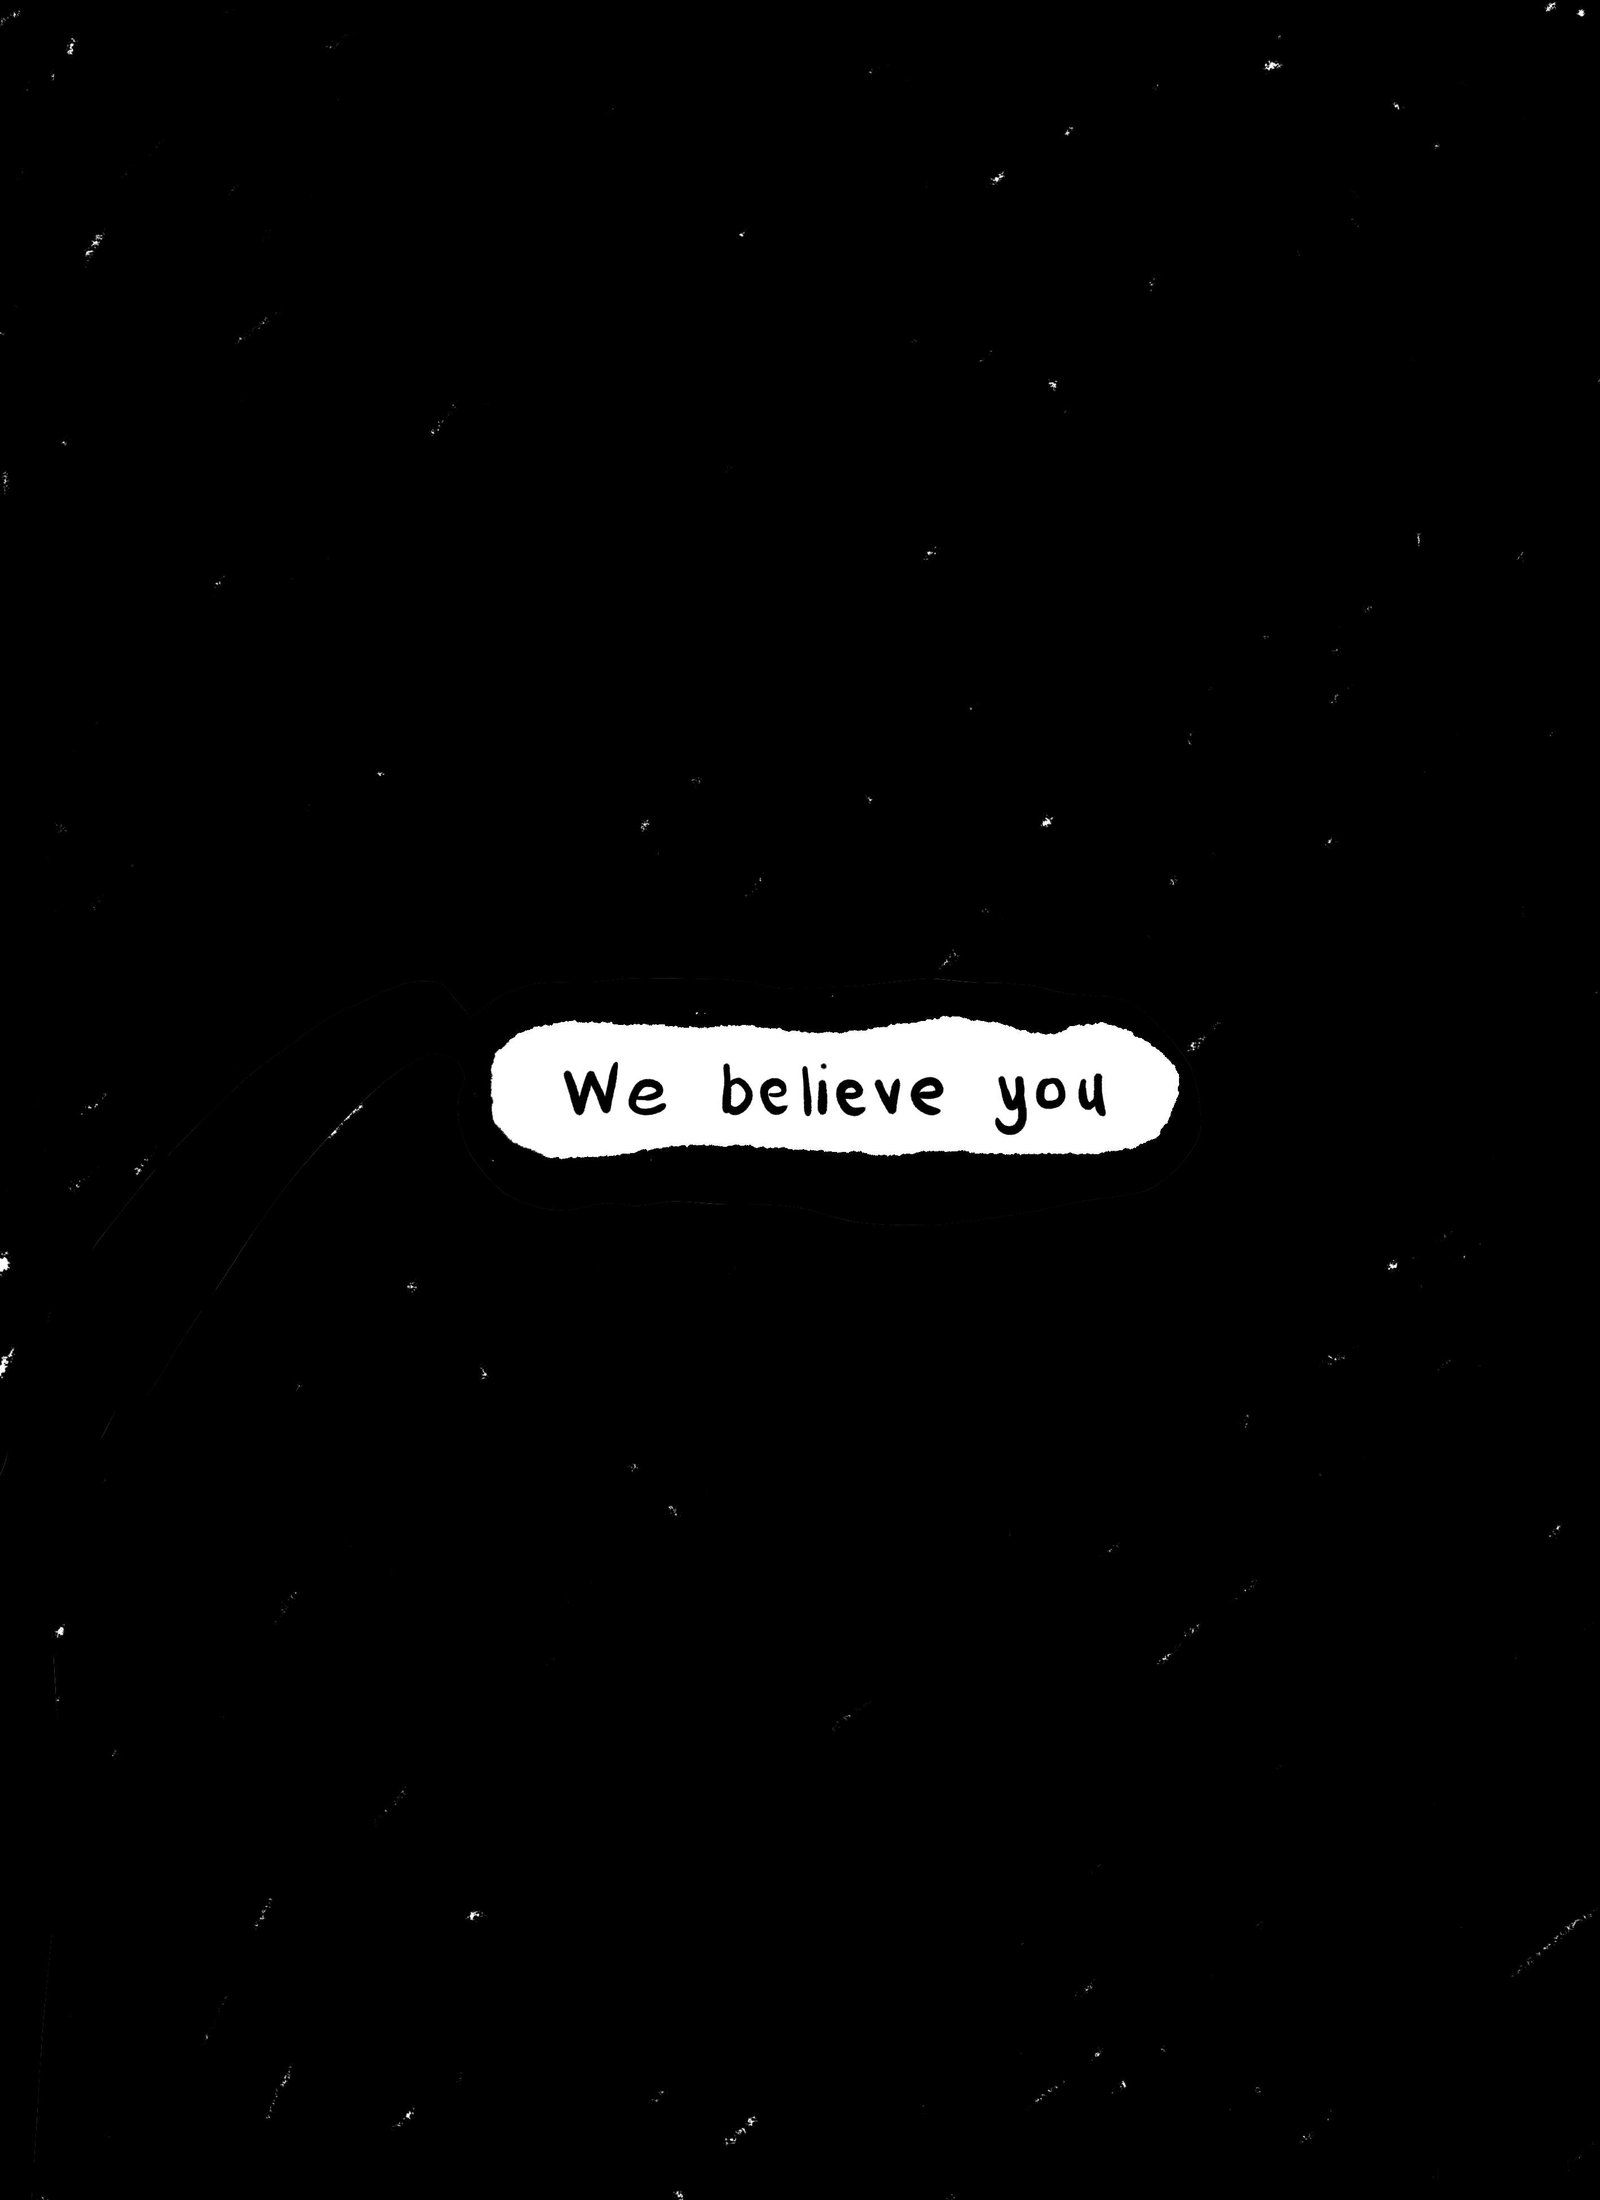

We believe you